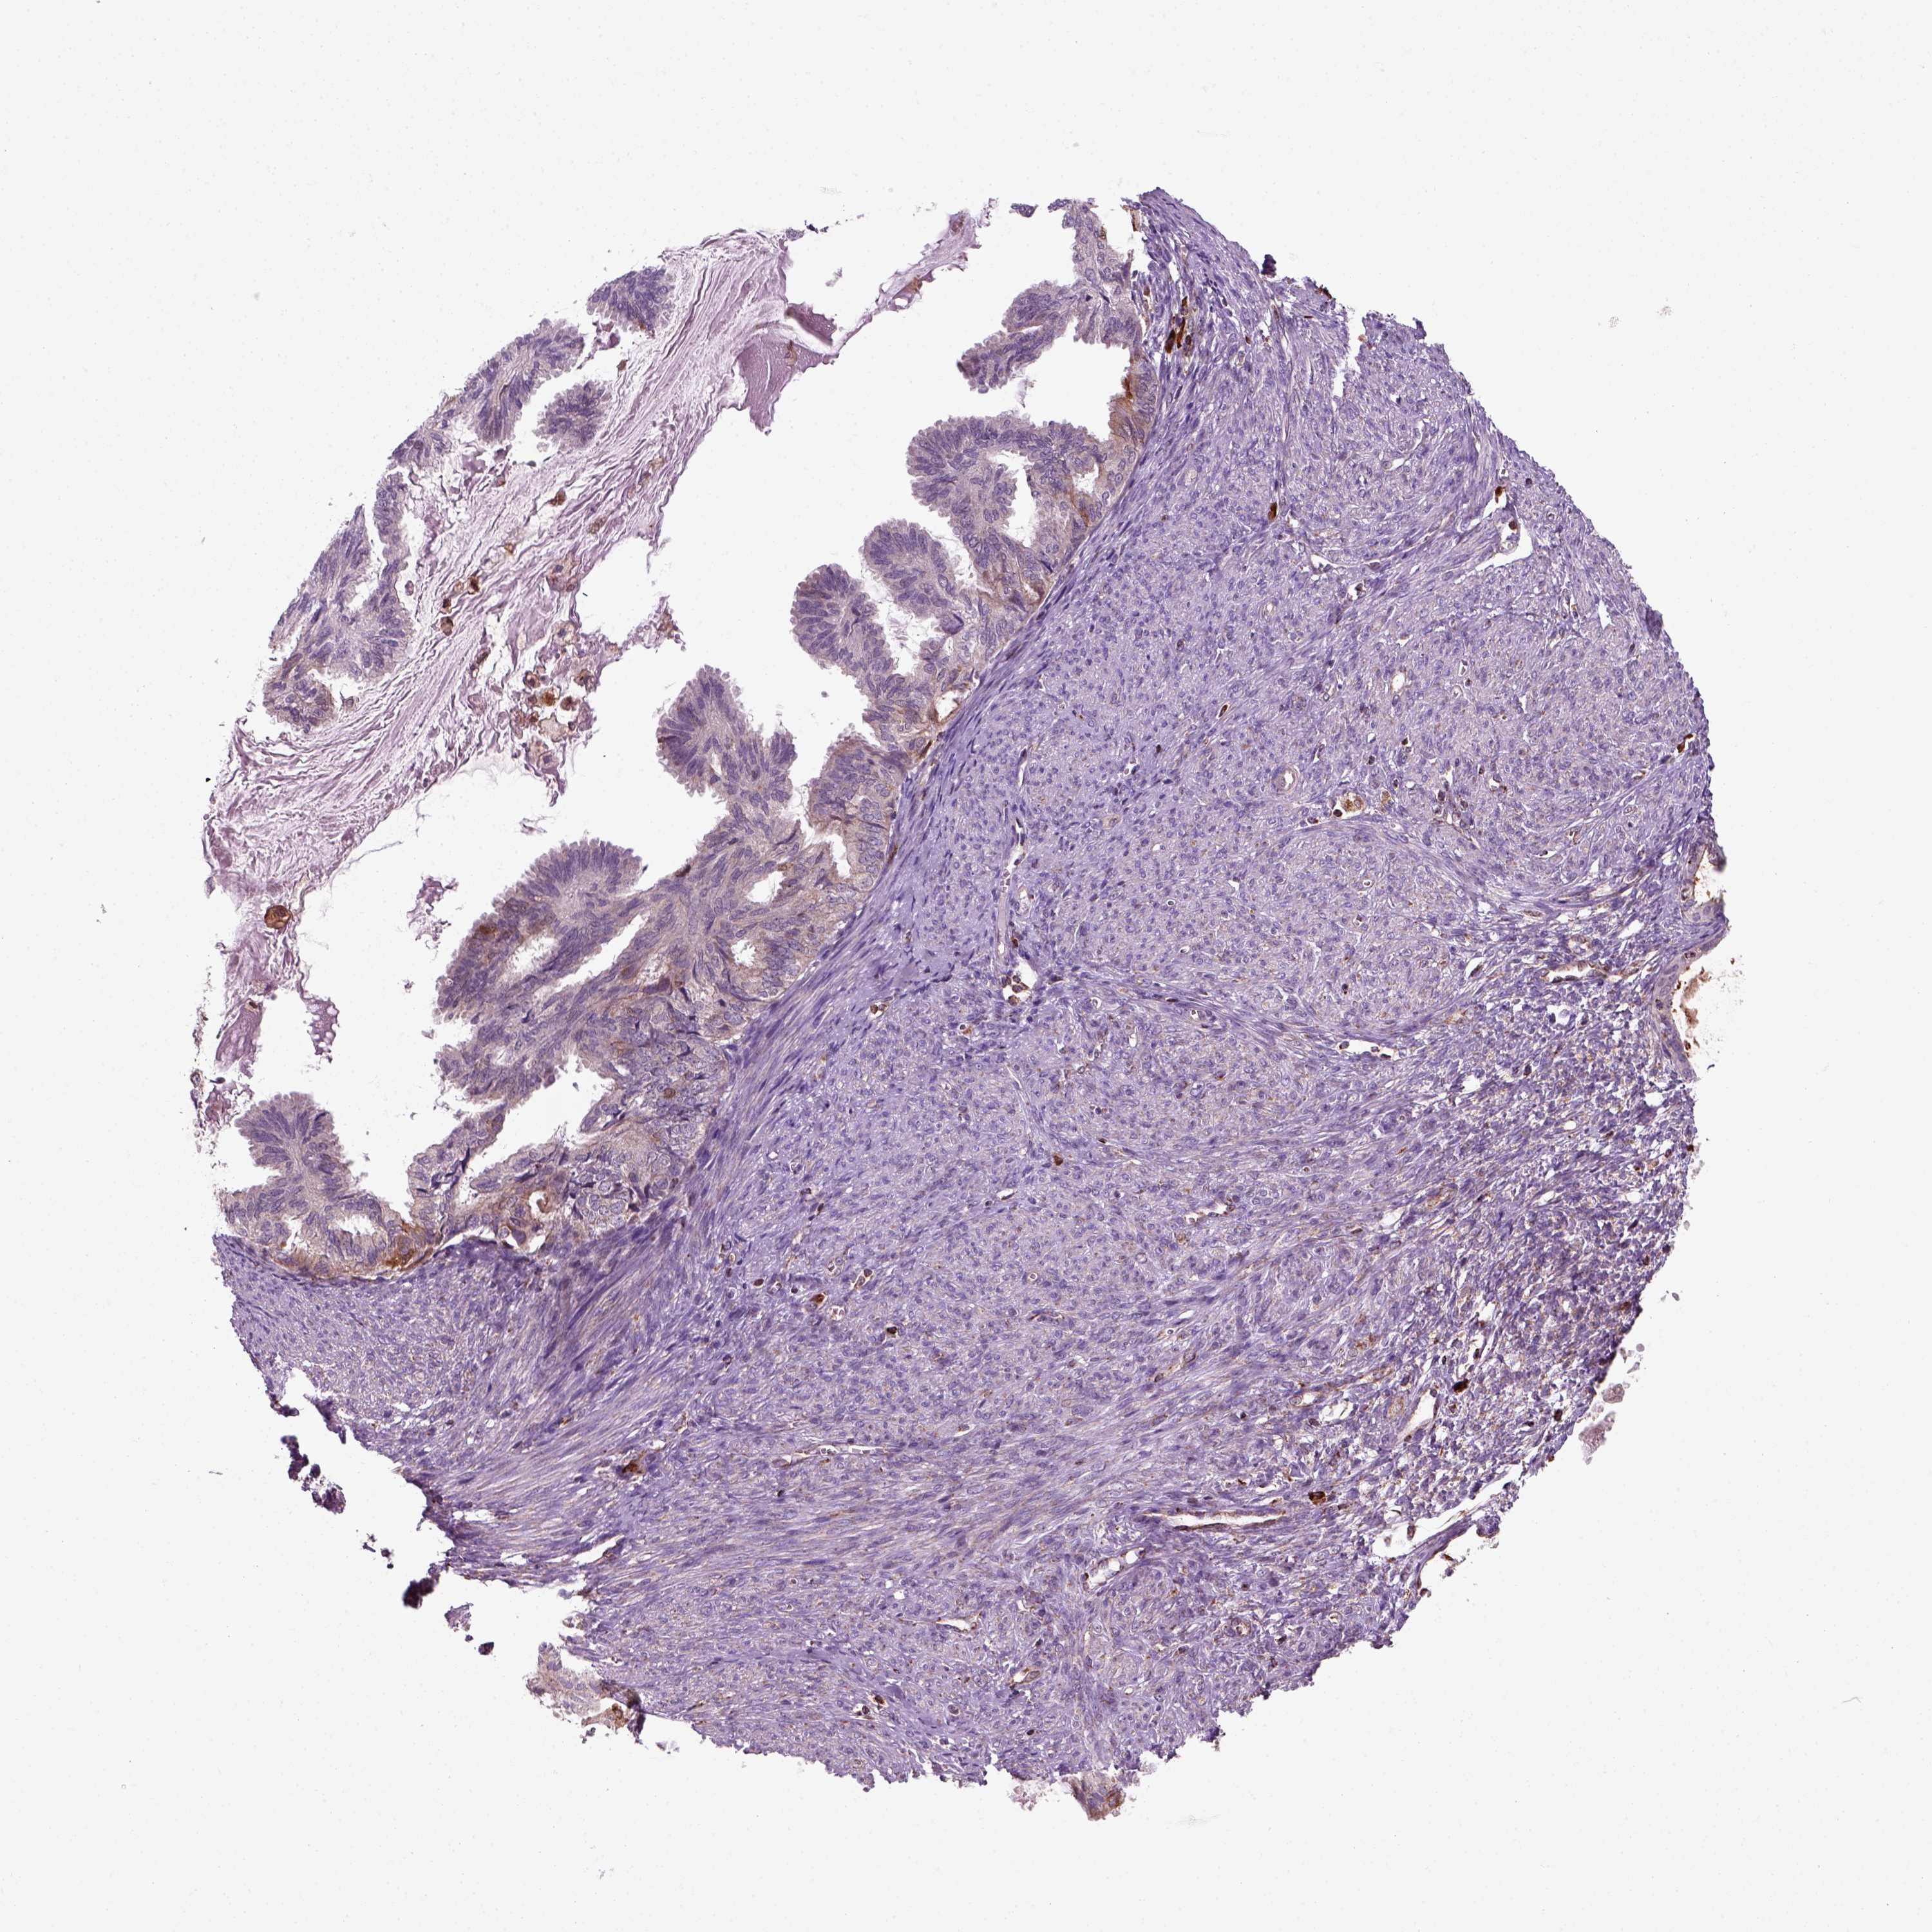

ENDOMETRIAL CANCER - Protein expressioni

A mouse-over function shows sample information and annotation data. Click on an image to view it in a full screen mode. Samples can be filtered based on level of antibody staining by selecting one or several of the following categories: high, medium, low and not detected. The assay and annotation is described here.

Note that samples used for immunohistochemistry by the Human Protein Atlas do not correspond to samples in the TCGA dataset.

Antibody stainingi

Antibody staining in the annotated cell types in the current human tissue is reported as not detected, low, medium, or high, based on conventional immunohistochemistry profiling in selected tissues. This score is based on the combination of the staining intensity and fraction of stained cells.

Each image is clickable and will lead to virtual microscopy that enables deeper exploration of all samples and also displays staining intensity scores, fraction scores and subcellular localization as well as patient and tissue information for each sample.

Antibody HPA044186

Antibody HPA063605

Staining

High

Medium

Low

Not detected

Intensity

Strong

Moderate

Weak

Negative

Quantity

>75%

75%-25%

<25%

None

Location

Nuclear

Cytoplasmic/membranous

Cytoplasmic/membranous,nuclear

Adenocarcinoma, NOS

Adenocarcinoma, metastatic, NOS